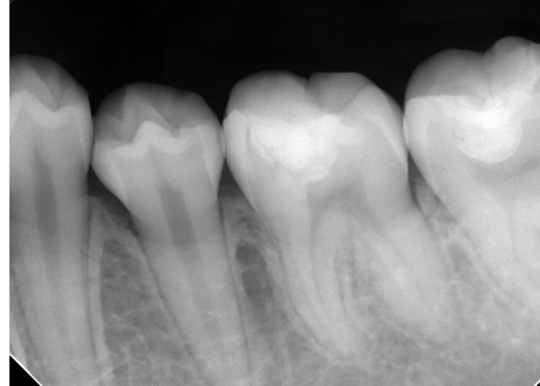

自費根管治療症例1 治療前

左上の奥歯の腫れと噛んだ時の痛みで来院。

根の先にうみが溜まっています

副鼻腔の骨の壁を突き破っています